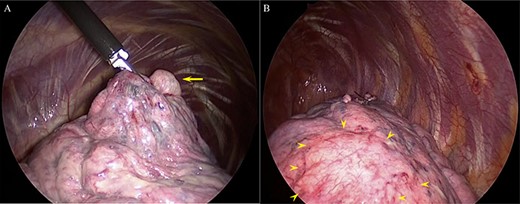

Histopathological findings showing a pulmonary bulla (asterisk in (A) and (B)). (A) Hematoxylin-Eosin stain. (B) Elastica van Gieson stain.

recurrent intermittent epistaxis every few months and was monitored for PAVMs using computed tomography (CT) examinations every 6 months. He had a family history of HHT in his father and grandfather. After systemic examinations, he was diagnosed with HHT because he met the diagnostic criteria, including the presence of PAVM, recurrent epistaxis, and a family history of HHT, although genetic testing was not performed. A chest CT scan showed a left pneumothorax and apical bullae on both sides of the upper lobe (Fig. 1). In addition, a total of six PAVMs (four in the right lung, two in the left lung) were shown on the chest CT (Fig. 2). All PAVMs were located peripherally with the largest one being 3 mm in diameter. No AVM was detected in the brain or abdomen on CT. He was treated conservatively and then pneumothorax was improved. Six months later, the patient complained of cough and was diagnosed with pneumothorax by chest X-ray. To prevent the recurrence of the pneumothorax, the patient was offered video-assisted thoracic surgery. Intraoperatively, apical bullae and multiple telangiectasias were identified under the visceral pleura (Fig. 3). We performed wedge resection of the left upper lobe including the apical bullae. The postoperative histopathological findings of the resected specimen revealed pulmonary bullae (Fig. 4). The postoperative course was uneventful, and the patient was discharged on postoperative Day 2. He underwent catheter embolization for PAVMs in another hospital. His SpO2, which was measured before catheter embolization, was 97% on room air. There was no remarkable change in SpO2 after the intervention. No recurrence of the pneumothorax was observed during a 3-year follow-up.

The histopathological findings of the resected lung specimen could not indicate an association between the cause of pneumothorax and abnormal blood vessels in our patient. The multiple bullae on the bilateral apical lungs had presented before pneumothorax onset, indicating that the spontaneous pneumothorax occurred with no specified etiology in our patient.